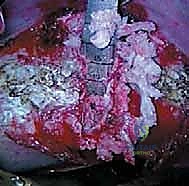

ثامناً: الخطوات الجراحية التفصيلية لعملية الدمج الفقري الأمامي

هذه العملية هي تحفة فنية هندسية وطبية. إليكم كيف يقوم الأستاذ الدكتور محمد هطيف وفريقه الجراحي المتميز بتنفيذها خطوة بخطوة في أفضل مستشفيات صنعاء المجهزة.

الخطوة 3: الشق الجراحي والوص